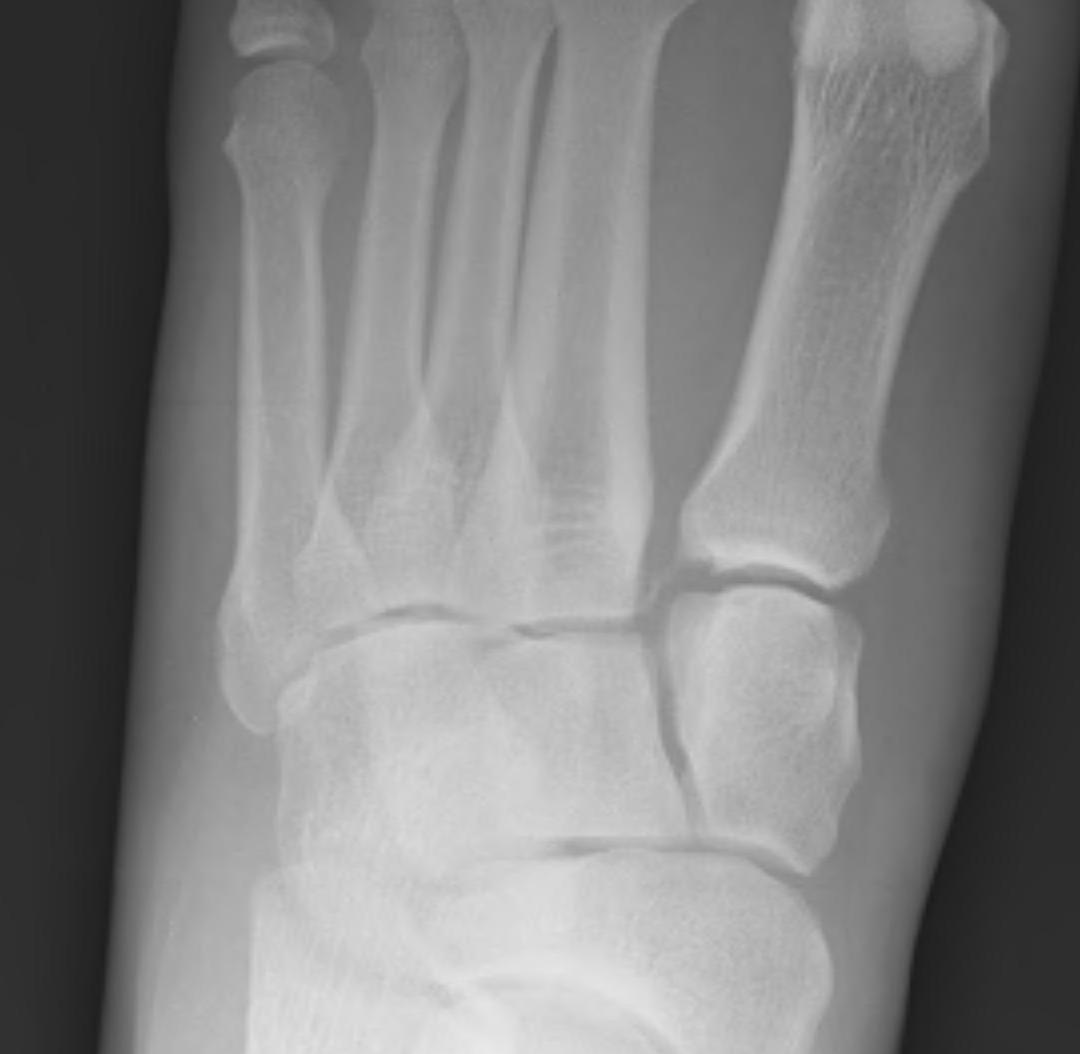

Widening of the medial cuneiform - 2nd metatarsal distance, inter-metatarsal diastasis, fleck sign, possibly increased inter-cuneiform distance

- medial border 4th metatarsal aligns with medial border of the cuboid (oblique view)